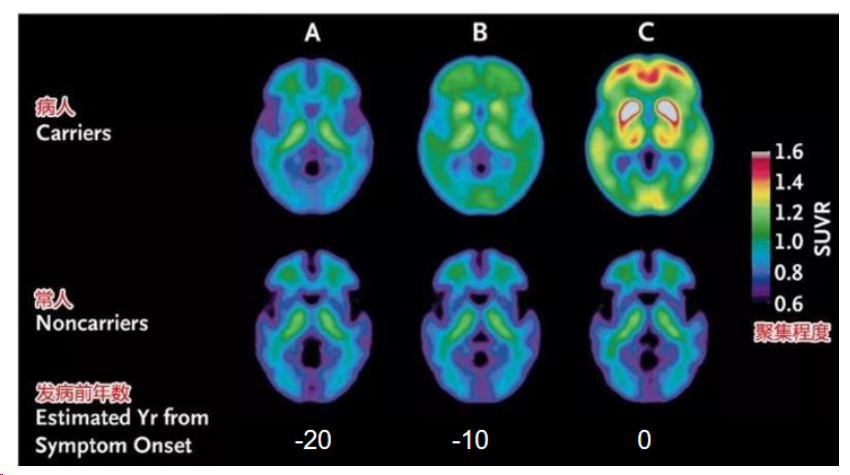

大脑中β-淀粉样蛋白斑块和神经纤维缠结导致脑细胞通信受阻,最终引发脑部萎缩。目前具体触发机制尚不明确,但遗传因素可能增加风险。